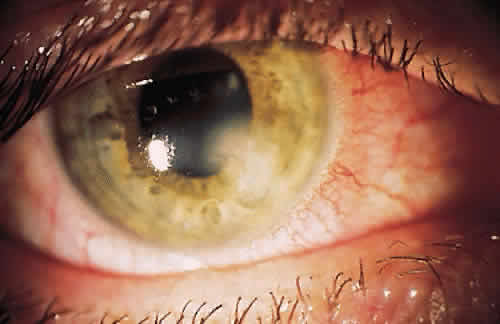

If the organism is able to make it through the lashes, past the skin and tear film, it reaches yet another barrier, the conjunctiva. Mucin secreted from goblet cells in the conjunctiva can inhibit the penetration of cells by viruses through competition with cell surface receptors for the viral neuraminidase.12 The conjunctiva is also able to increase blood flow in the presence of irritants that may represent potentially infectious agents. The blood contains products that participate in natural and humoral immunity.